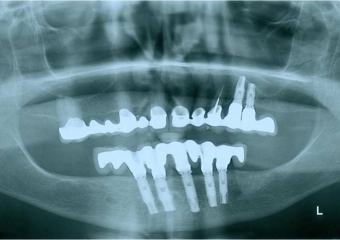

Raio X de controle, realizado em Setembro de 2008